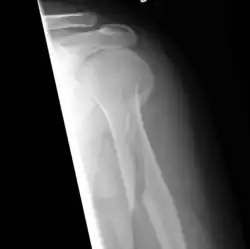

Fractura espiroidea del húmero

En medicina y traumatología, se designa con el nombre de fractura espiroidea a aquella fractura ósea en la cual la línea de fractura sigue una dirección espiral en relación con el eje principal o longitudinal del hueso. Se llama en ocasiones fractura por torsión en base al mecanismo de producción. Afecta fundamentalmente a los huesos largos como el húmero y la tibia.[1]